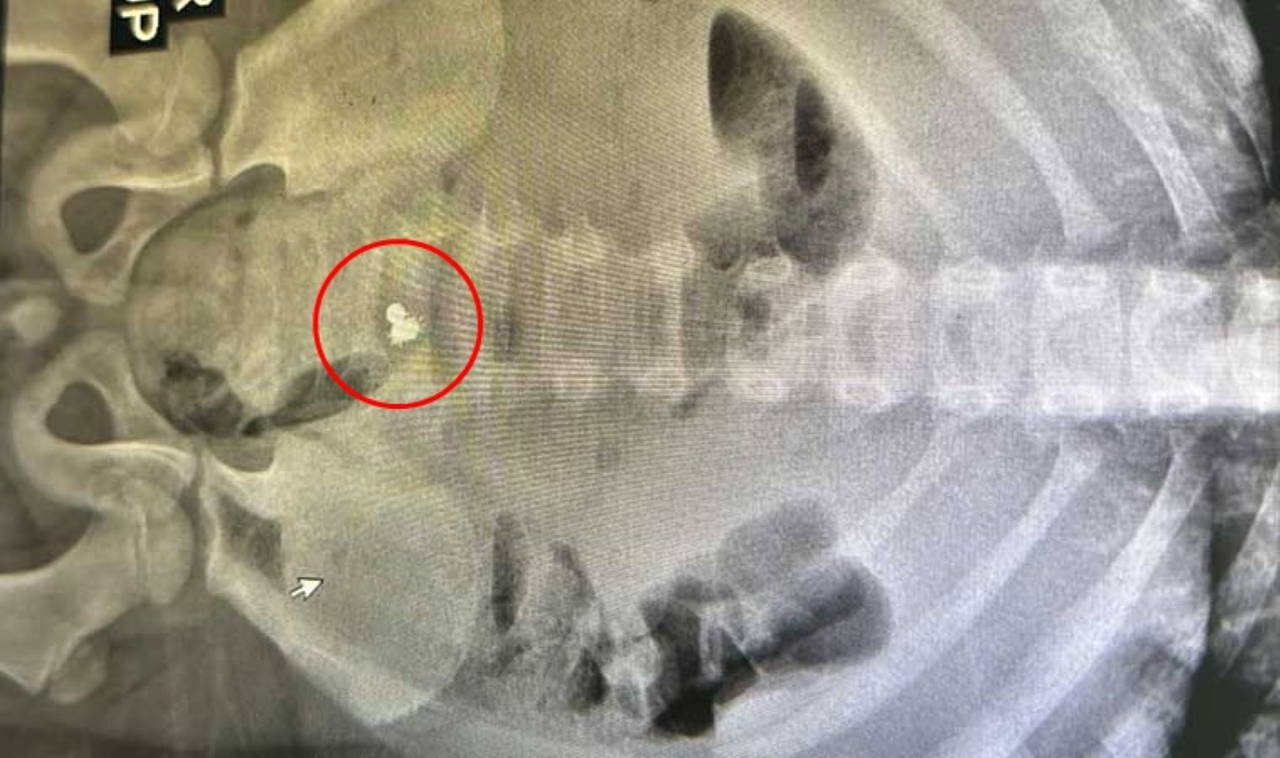

Elif ve Orhan Kalay çifti, bulantı ve kusma şikayetleri olan 7 yaşındaki oğulları Miraç'ı, hastaneye götürdü. Çekilen röntgende bağırsağına yapışmış 3 parça mıknatıs tespit edilen çocuğun ameliyatına karar verildi.

Cerrahi Tıp Bilimleri Bölümü Çocuk Cerrahisi Anabilim Dalı Dr. Öğr. Üyesi Halil İbrahim Çakmak ve ekibi tarafından gerçekleştirilen operasyonla mıknatıslar çıkarılarak Miraç'ın üç yerden delinen bağırsağı dikildi. Tedavinin ardından sağlığına kavuşan çocuk, birkaç gün içinde taburcu edilecek.